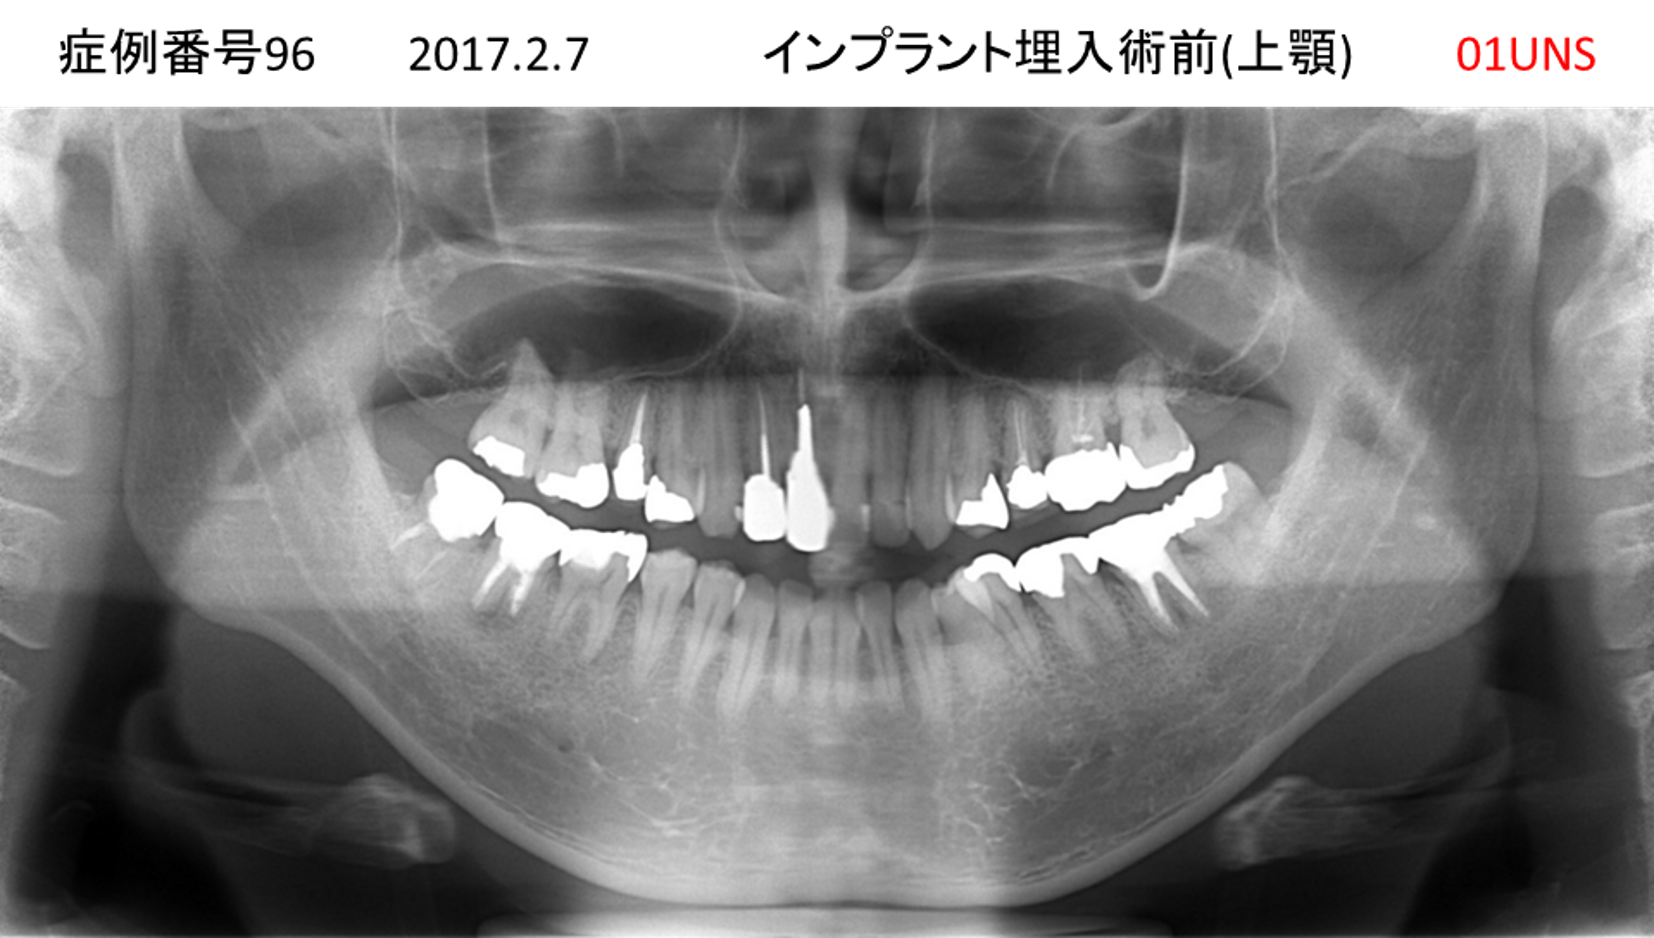

上の前歯が揺れてきてかめない患者様のインプラント症例

| 治療名称 |

インプラント |

| 治療費用 |

440万円+税 |

| 治療期間 |

6か月 |

| 患者さんの症状(主訴) |

上の前歯が揺れてきた。かめない |

| 治療内容 |

サイナスリフト、GBR、インプラント、即時荷重 |

| 治療結果 |

上の前歯の揺れが収まった。奥歯でしっかり噛める。 |

| 治療の注意点(リスク/副作用) |

インプラントが壊れたら再治療が必要 |